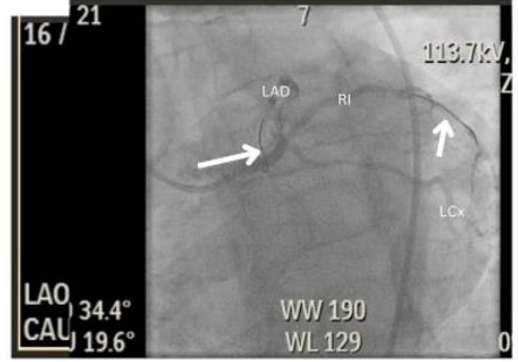

Figure 3: Left anterior oblique caudal view. This angiographic image shows the stented mid- ramus intermedius (white arrow).

Two days subsequent to his second percutaneous coronary intervention (PCI), another rapid response was called for the patient for complaints of classical anginal chest pain. An EKG was promptly obtained which showed mild STE in AVL with ST depressions in the inferior leads/III and AVF and a Hs trop of >5000. Given these findings, he was emergently transported to the catheterization laboratory and was found to have a recurrent late*** stent thrombosis of both Left anterior descending and Ramus Intermedius stents requiring PTCA and IVUS guided optimization of both stents (Figure 8). He was then placed on the eptifibatide infusion, and this time round was started on Prasugrel, instead of Ticagrelor, along with ASA. In addition, triple anticoagulation therapy was recommended for the patient and had 2.5mg rivaroxaban daily added to his Dual-Antiplatelet therapy.